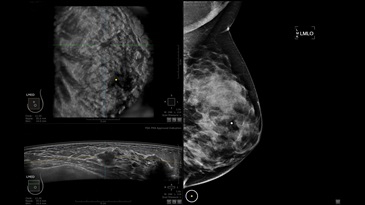

GE INVENIA ABUS – это современный УЗИ аппарат, который создан для точной и эффективной диагностики сканирования с высокой плотностью молочных желез. Выявляемость патологий раковых и предраковых стадий заболевания составляет 55%, что в конечном счете позволяет ставить врачу точные и своевременные диагнозы. Традиционные методы использования маммографии не показывают такой выявляемости, ограничиваясь лишь 3-38%.

УЗИ-аппарат GE INVENIA ABUS позволяет проводить максимально операторонезависимые процедуры, что значительно снижает риск неправильной постановки диагноза и сопутствующие издержки на обработку информации. Система готовит отчет в течение 3-х минут после сканирования, это безусловное преимущество по сравнению с обычным УЗИ сканером.

Области применения: ультразвуковой скрининг заболеваний молочных желез.

• Получение изображений в поперечной плоскости (в реальном времени) и в коронарной плоскости (статическая, для указания нахождения соска)

• Отображение объемных 3D ультразвуковых изображений, которые состоят из традиционных поперечных и воссозданных коронарных и сагиттальных проекций

• Стандартизованная ориентация изображения: «толстый срез» в коронарной плоскости; поперечная; сагиттальная плоскость; радиальный и антирадиальный поворот изображения; просмотр исключительно области интереса